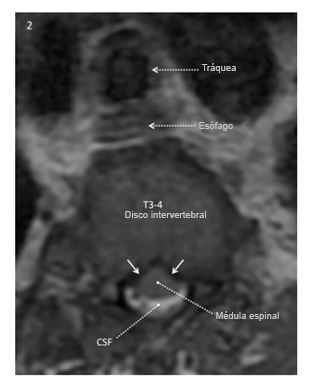

La imagen ponderada axial T2 al nivel del disco intervertebral T3-4 obtenida 7 meses antes de la operación muestra fluido cerebroespinal (blanco) alrededor de la parte posterior de la médula espinal, no de la anterior. La superficie anterior de la médula tiene una configuración en forma de “carpa” en lugar de una configuración suave convexa, lo que refleja presión ventrolateral bilateral en la superficie anterior de la médula (flecha blanca sólida).

Reproducido con permiso de Drummond, Can J Anesth, 2015.

Recuperación de inversión T2 sagital /T1 corta ―imagen ponderada de la columna torácica y lumbar obtenida 7 meses antes de la operación.

Reproducida con permiso de Drummond, Can J Anesth, 2015.